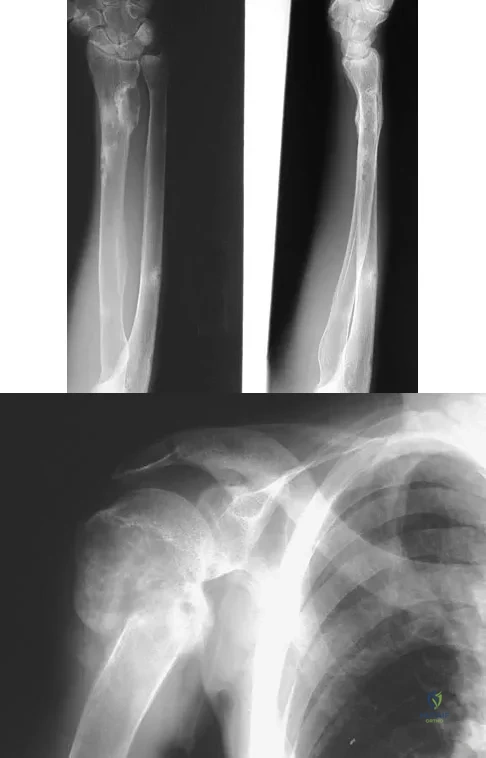

A 29-year-old woman reports shoulder pain after sustaining a minor fall 6 weeks ago. She has a history of celiac sprue. Radiographs of the forearm and shoulder are shown in Figures 53a and 53b. Which of the following serum abnormalities would be expected?

Figures 20a through 20c show the radiographs of a 69-year-old woman who has severe pain in her dominant right arm after falling on the ice. History includes arthritis, hypertension, and heart disease. She is neurovascularly intact. Management should consist of